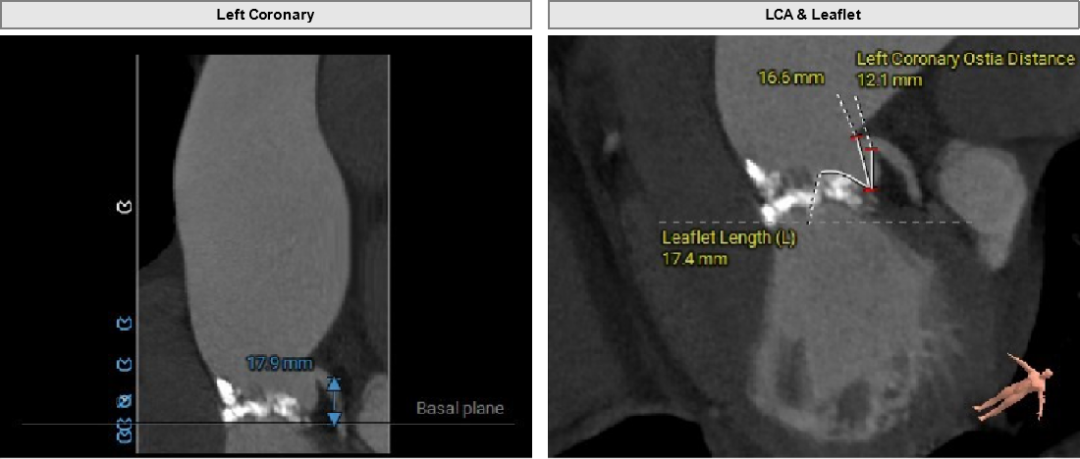

主动脉根部评估

Type1型左右融合二叶式主动脉瓣。

瓣环周长84.7mm,平均周长径27.0mm。

左冠高度17.9mm,右冠高度13.5mm。

瓣口对应瓣叶稍冗长,术中须注意冠脉风险。

主动脉弓角度与宽度可,心脏水平夹角68°,横位心。